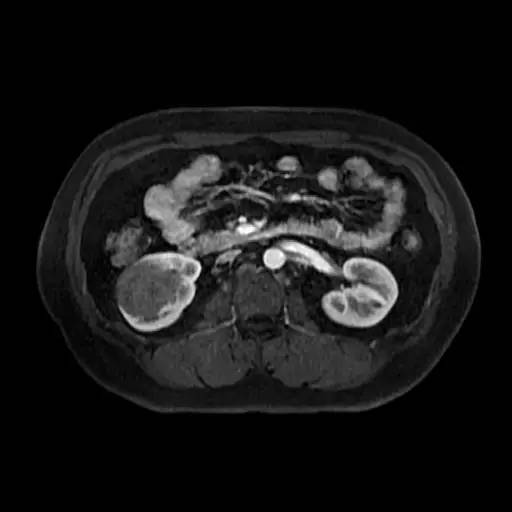

右肾中下部见类圆形约52*49*59毫米类圆形短和稍长T1、短和长T2异常信号肿块,可见假包膜,DWI呈晕环结节状稍高和稍低信号,反相位图像病变信号未见异常减低;皮质期病变未见异常强化,髓质期及延迟期持续轻度强化;病变内小部分区域未见强化。所见肝胆、胰腺、脾脏及双侧肾上腺未见异常,肝门、肾门及所见腹膜后未见异常肿大淋巴结影。

影像诊断:右肾中下部少血供肿块伴出血、坏死和囊变,考虑:恶性肿瘤,以肾癌(非透明细胞癌)可能性最大,不能完全除外表现不典型的血管平滑肌脂肪瘤。